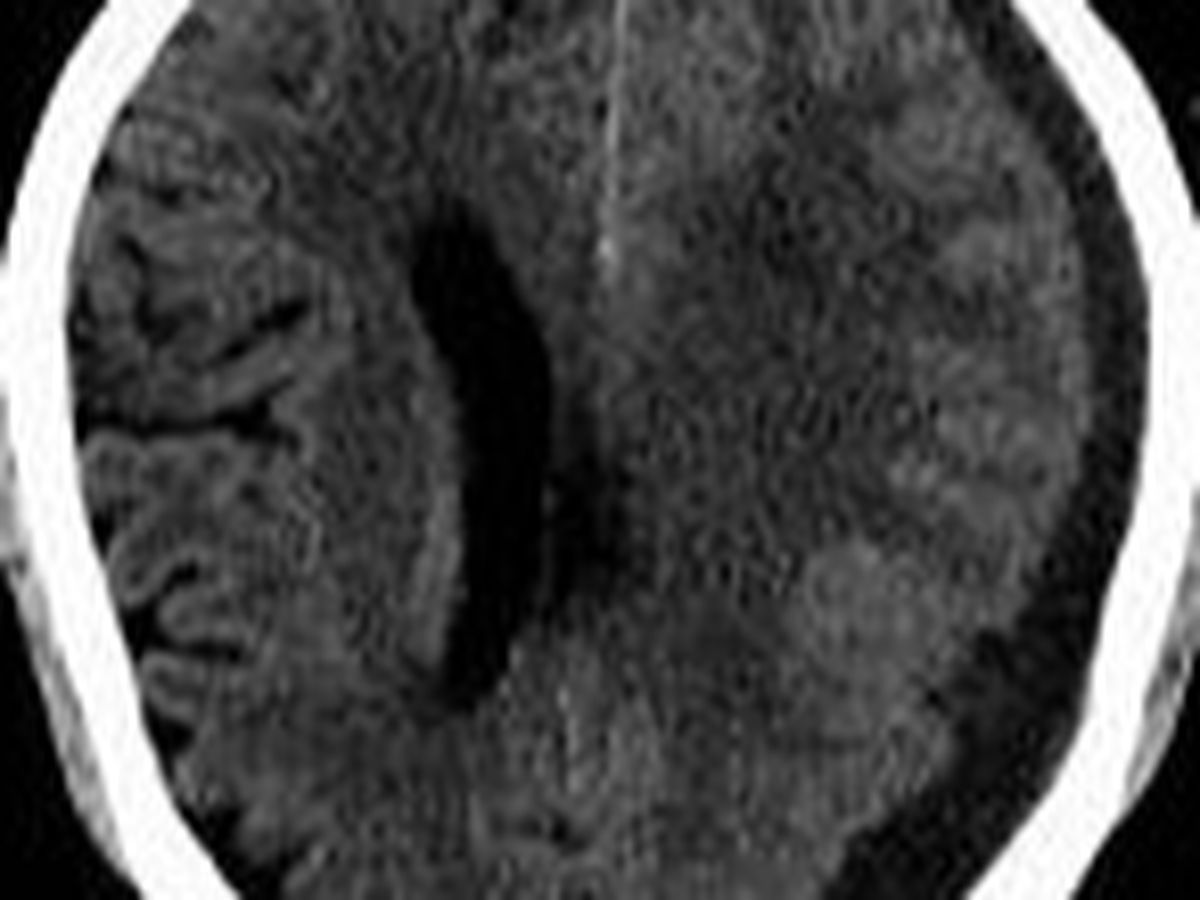

Chronic Subdural Hematoma is a serious medical condition in which blood accumulates between the brain's surface and its outermost covering. This condition often results from head injuries, and it can lead to severe headaches, cognitive impairments, and even life-threatening complications. Abid's condition has unfortunately progressed to a critical stage, making it difficult for him to carry out even the simplest daily activities.